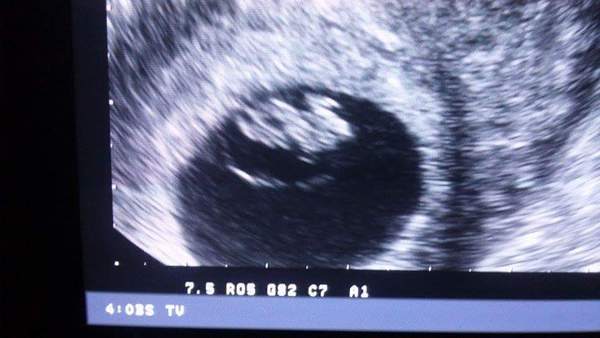

Has my scan today 7+3 week and there was a heartbeat this time so made up roll on 1st Dec for my 12 week scan to see my peanut again

Our peanut my dh said it looked like a frog lol but he got a bit emotional bless him x

After my emotional meltdown on Tuesday, I started spotting on Weds morning. So worrying - that's exactly how my miscarriage began last time. GP arranged a scan today, and they saw a sac, a little embryo and a heartbeat! Smile they also saw a v small haematoma which they thought was causing the spotting but didn't seem worried by it at all.

clarish .. Thats a gorgeous scan picture Smile .. Yesterday my DH said he didnt want to come for the reassurance scan because he thought I was being a paranoid idiot (which is true) but like yours he got emotional too when I showed him the scan picture. You could just see the regret on his face, bless him! Its the best thing in the world to see that heartbeat, isnt it? Smile

Lovely scan pic clarish xx

Lovely pic Clarish how exciting